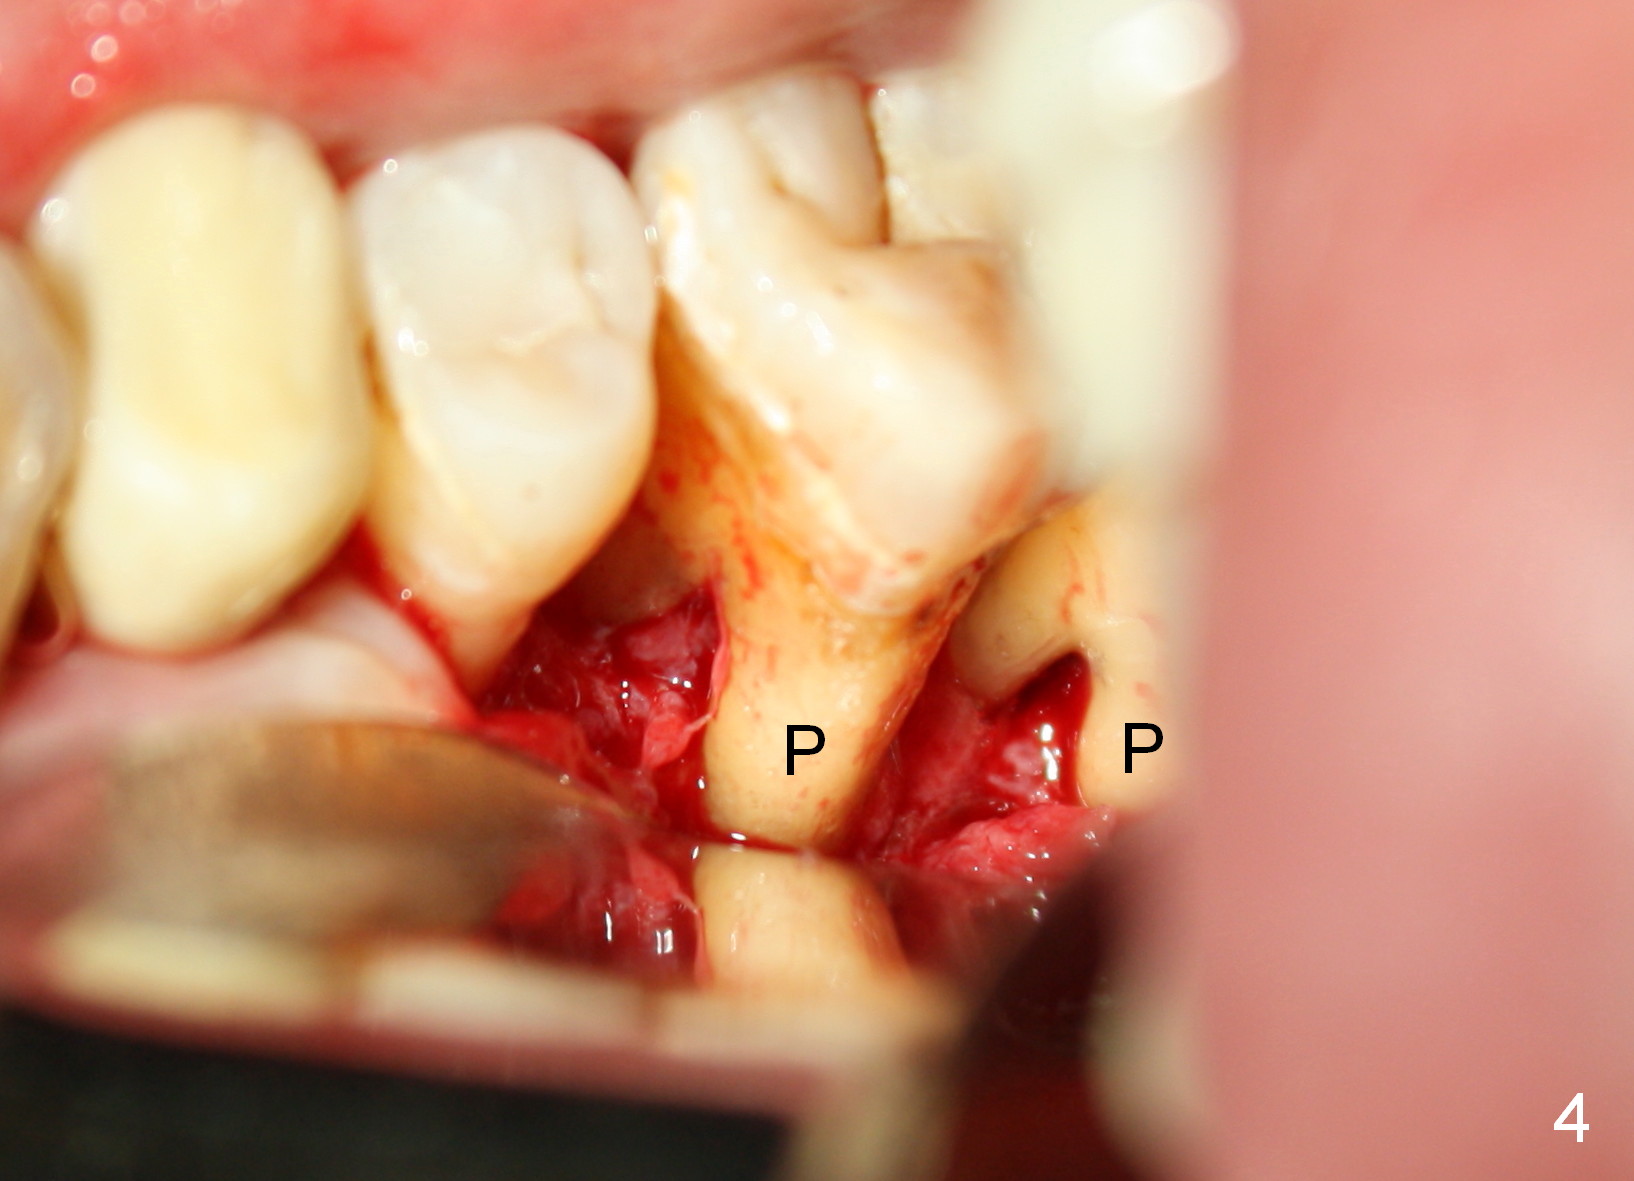

A 41-year-old man has chronic periodontits with bruxism. The teeth #14 and 15 are supraerupted (Fig.1 arrows) with furcal lesion (Fig.2 (CT) *). These 2 molars have guarded to poor prognosis. Due to insurance benefit limitation, we plan to save them temporarily with periodontal surgery so that bone loss would not get worse when the teeth are being intruded. After opposing implant placement (Fig.3), flaps are raised to remove calculus and granulation tissue (Fig.4, no bone graft). Twenty days later, three mini-implants are placed (Fig.5,6). The implant distopalatal to #15 is loose nearly 2 months postop (Fig.7 *) and retightened. The following month the same implant is placed higher for stability (Fig.8). The Intrusion takes <5.5 months (Fig.9,10).